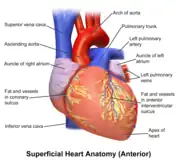

The heart has four chambers, two upper atria, the receiving chambers, and two lower ventricles, the discharging chambers. The atria open into the ventricles via the atrioventricular valves, present in the atrioventricular septum. This distinction is visible also on the surface of the heart as the coronary sulcus.[20] There is an ear-shaped structure in the upper right atrium called the right atrial appendage, or auricle, and another in the upper left atrium, the left atrial appendage.[21] The right atrium and the right ventricle together are sometimes referred to as the right heart. Similarly, the left atrium and the left ventricle together are sometimes referred to as the left heart.[6] The ventricles are separated from each other by the interventricular septum, visible on the surface of the heart as the anterior longitudinal sulcus and the posterior interventricular sulcus.[20]

| Artery | Aorta,[lower-alpha 1] pulmonary trunk and right and left pulmonary arteries,[lower-alpha 2] right coronary artery, left main coronary artery[lower-alpha 3] |

| Vein | Superior vena cava, inferior vena cava,[lower-alpha 4] right and left pulmonary veins,[lower-alpha 5] great cardiac vein, middle cardiac vein, small cardiac vein, anterior cardiac veins[lower-alpha 6] |